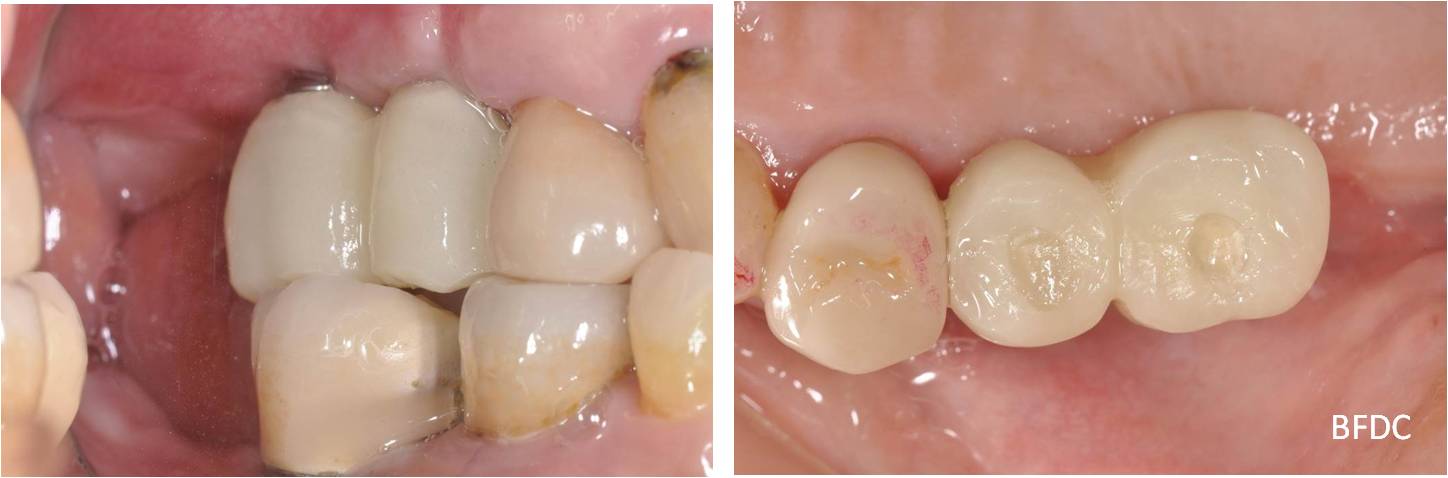

治療前,牙齦下蛀牙,牙齒動搖

術前、術後比較